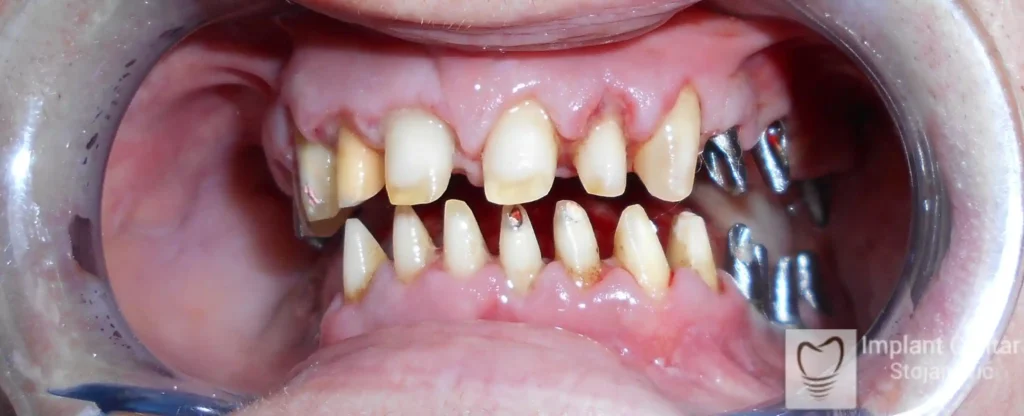

U ovom slučaju prikazujemo potpunu transformaciju osmeha pacijenta koji je imao obrnut zagriz koji smo rešili trajno i funkcionalno pomoću implantata.

Na slici 1. slici 2. vidi se početno stanje — pacijent je imao prirodne zube, ali samo izradom novih mostova nije bilo moguće postići normalan odnos gornjih i donjih zuba (eugnatan zagrižaj).

Zbog toga je plan terapije uključivao vađenje svih preostalih zuba i ugradnju implantata u gornjoj i donjoj vilici. U gornjoj vilici postavljena su i dva tuberopterigoidna implantata, kao zamena za sinus lift proceduru, što se može videti na ortopan snimku nurađenom odmah nakon ugradnje (slika 3).

Već tri dana nakon operacije, pacijent je zbrinut fiksnim privremenim zubima na implantatima, čime je odmah povraćena funkcija i estetika osmeha.

Nakon završetka perioda integracije implantata, izrađeni su cirkonijum-keramički mostovi u gornjoj i donjoj vilici (slika 6.).

Pacijent ističe da je prezadovoljan rezultatom — po prvi put nakon dugo vremena može normalno da žvaće i grize hranu, uz prirodan izgled novog osmeha.